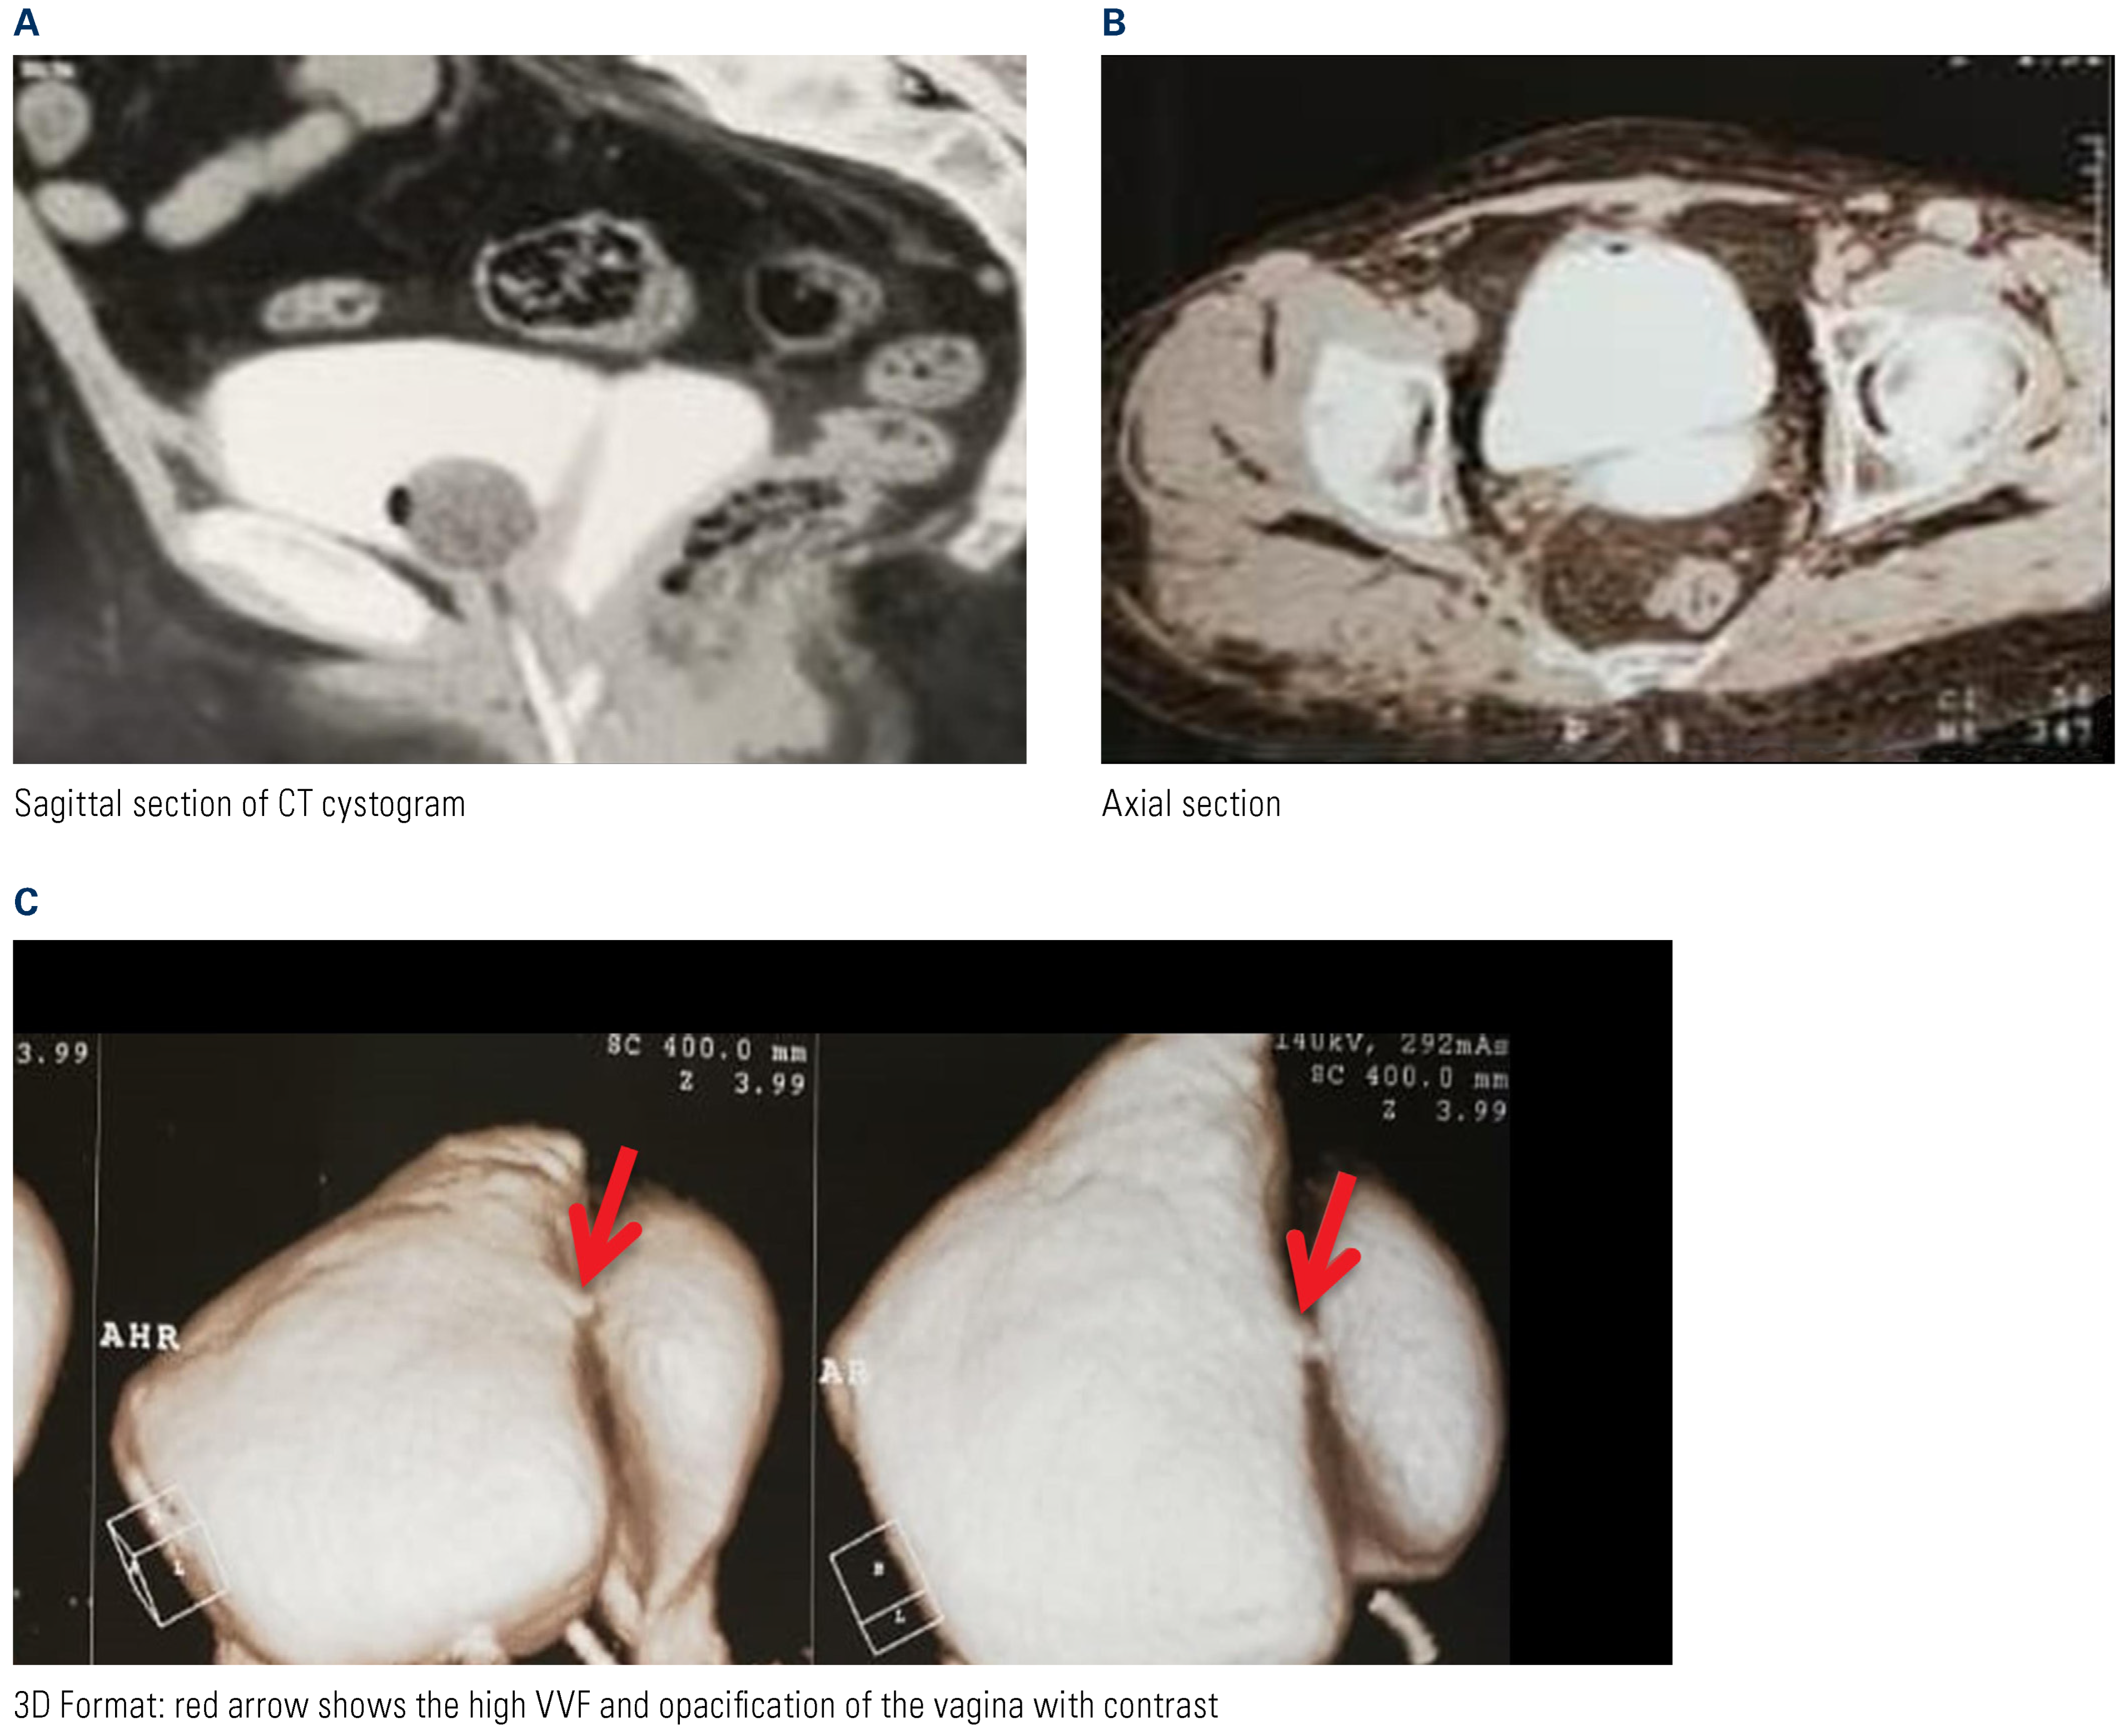

Between 2013 and 2018, 94 consecutive female patients with high vesicovaginal fistula or previous vaginal surgery that precluded transvaginal fistula repair were randomized to fistula repair by an extravesical transabdominal technique (n = 47) or by a transvesical transabdominal technique (n = 47) at our center. Preoperative patient evaluation included history, physical examination (local vaginal examination, inspection with speculum, dye test), and CT cystogram (Figure 1). Informed consent was obtained from all patients prior to surgery, and institutional review board approval was granted.

Figure 1.